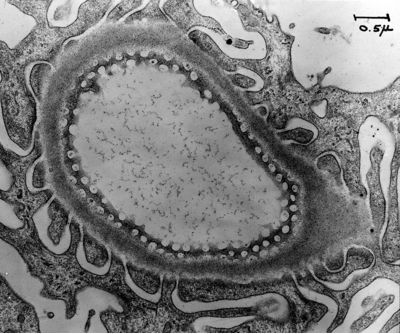

The collection of images includes some of the earliest electron micrographs taken by George Palade and his collaborators at the Rockefeller University (1945-1973) and at Yale University (1973-1990). Electron micrographs taken by Marilyn Farquhar (the glomerular basement membrane in renal filtration), Maya and Nicolae Simeonescu (capillary endothelium), James Jamieson (secretory pathway in the exocrine pancreas; atrial granules), Lucien Caro (electron microscopic autoradiography), Philip Siekevitz, John Bergeron and Japoco Meldolesi (microsomes, Golgi fractions), and Sanford Palay (synapses) are part of the collection.

| Farquhar, Marilyn G. - Kidney Rat glomerular filtration barrier tangential section fenestrated endothelium |